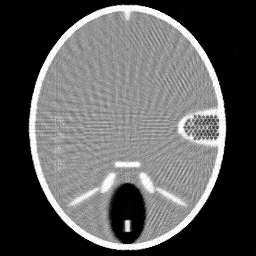

Figure 1. Phantoms for tests. (a) Head phantom used for simulation [24], (b) gel phantom used for real X-ray scan.

For the experiments, we test our method on a simulated head phantom from [24] and a real gel phantom shown in Figure 1. Here, we consider a 2D CT scenario. The detector has full coverage of the object at any projection angle, and a constant angular spacing of the rays is set in the interval of [0,π]0𝜋[0,\pi].